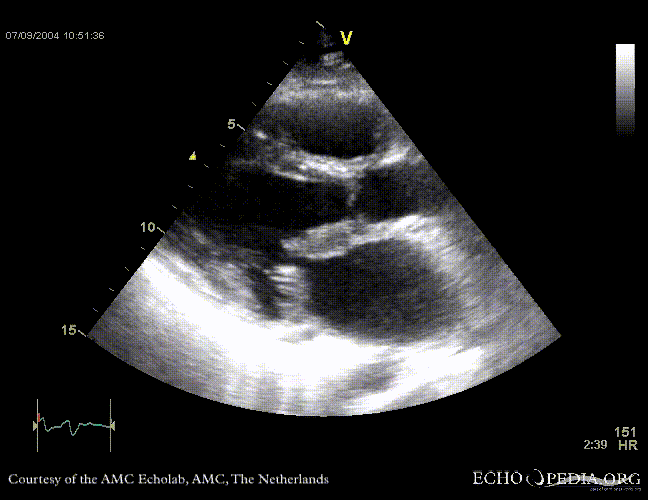

Case 11

| Courtesy of: J. Vleugels, AMC, The Netherlands | |

| <flash>file=E00152.swf | <flash>file=E00153.swf |

| Sarcoidose 7 | Sarcoidose 8 |